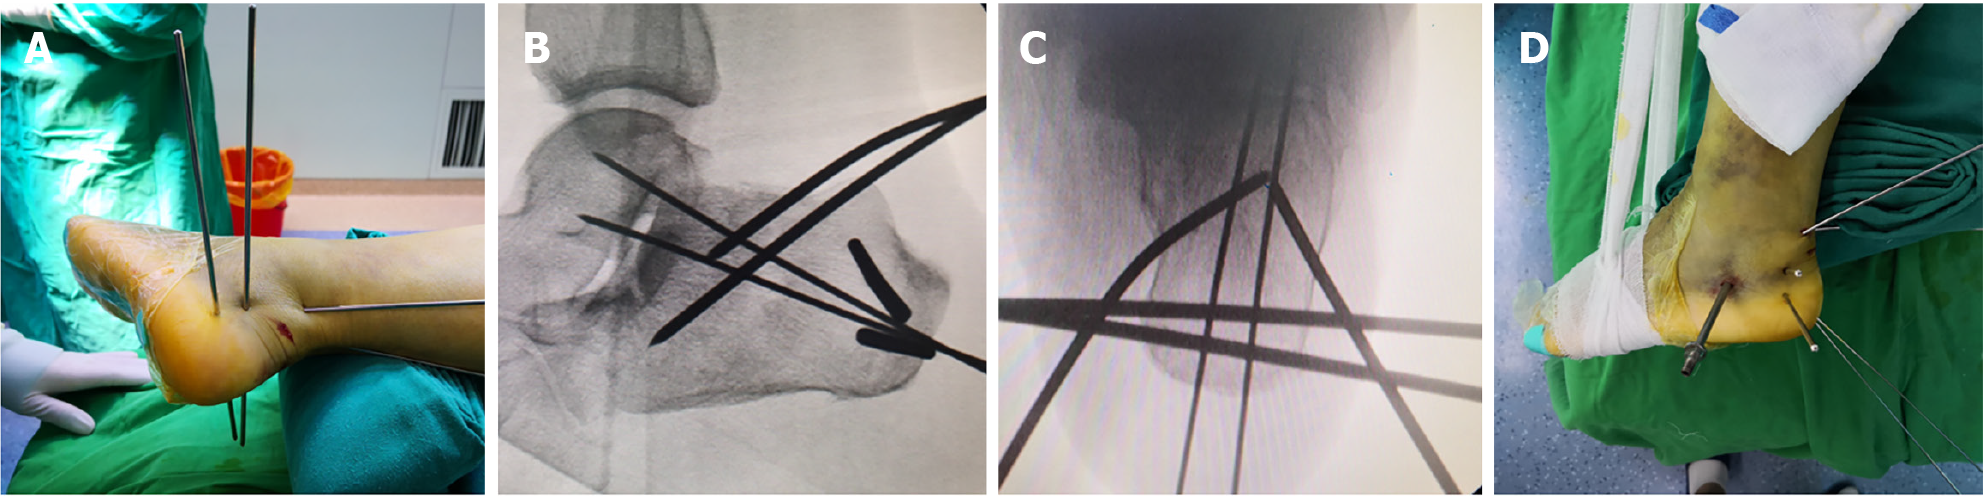

Figure 3 Step 1.

A: The preoperative plan specified a 40° prying angle with the entry point at the anterior margin of the calcaneal tuberosity. The tip of the Steinmann pin was positioned at the deepest point of the depressed fracture fragment; B: Two 2.0 mm Kirschner wires were placed superficially to simulate the intended trajectory and depth of insertion; C: Two 3.0 mm Steinmann pins were then inserted into the calcaneus with approximately 1.5 cm spacing between them, following the trajectory established by the superficial Kirschner wires; D: Fluoroscopic imaging confirmed satisfactory positioning of the superficial Kirschner wires.